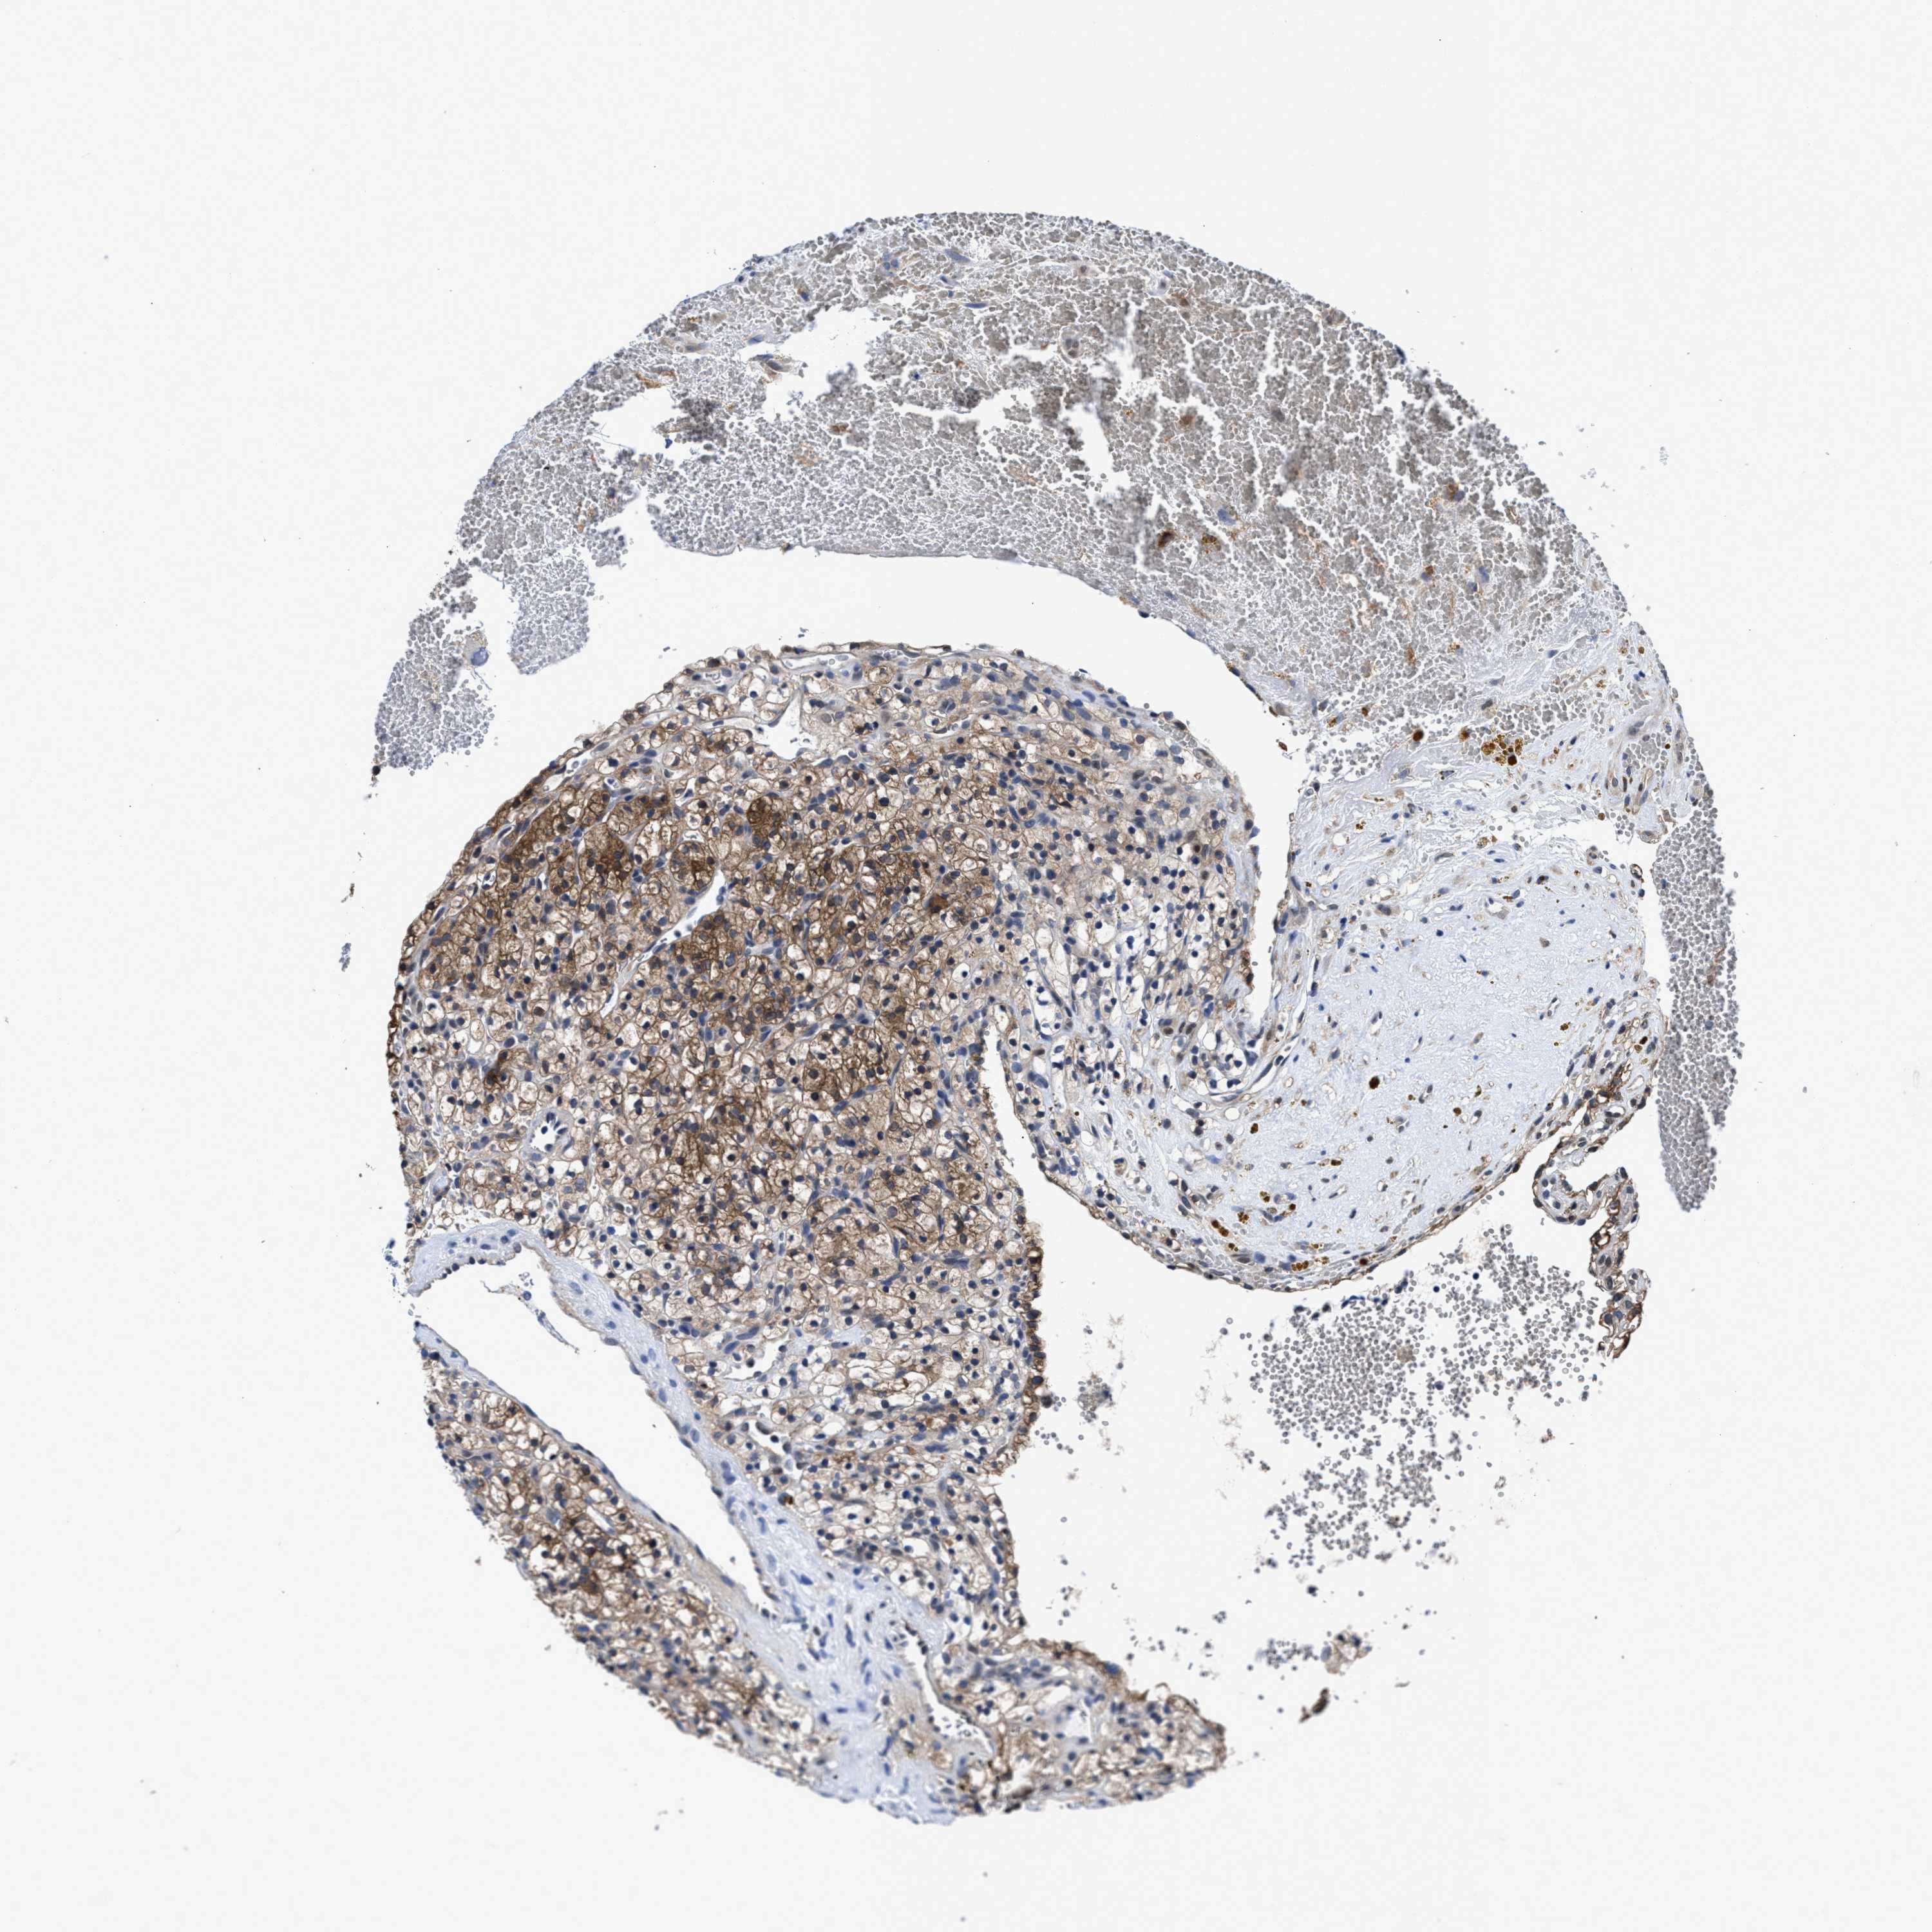

CANCER RENAL CANCER Show tissue menu

KICH TCGA KIRC TCGA KIRC VALIDATION KIRP TCGA PROTEIN RCC CPTAC PROTEIN EXPRESSION

ACLY is potential prognostic, high expression is favorable in Kidney Renal Clear Cell Carcinoma (TCGA)